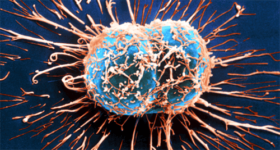

면역계는 외부 물질로부터 신체를 보호하는 것이 주된 기능인 복잡한 방어 시스템이다. 따라서 자체 성분을 외부 성분과 구별할 수 있는 것이 중요하다. 이는 면역계가 암과 싸우는 방식이다. 또한 면역계는 자체 세포 성분을 식별하고 싸울 수 있다. 이러한 성분이 비정상일 때 발생하며…